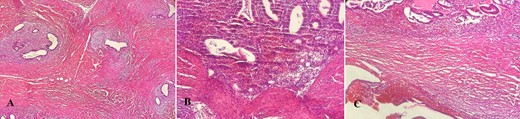

A physical examination revealed a palpable perianal mass with a size of ~4 cm, slightly tender on palpation extending to the anal sphincter. A scar from a previous incision was noticed, but no fluctuation or suppuration was noted. The patient was scheduled for elective surgery performed under general anesthesia. The mass was excised and the defect was closed primarily. The patient was discharged the following day after surgery. The histology revealed ectopic endometrial tissue composed of endometrial gland and stroma between collagen bundles with areas of hemorrhage with some siderophages (Fig. 2A–C).

Histopathology report (hematoxylin–eosin stain). (A) Endometrial ectopic tissue. (B) Areas of hemorrhage in ectopic endometrial tissue. (C) Hemorrhage in endometrial tissue.